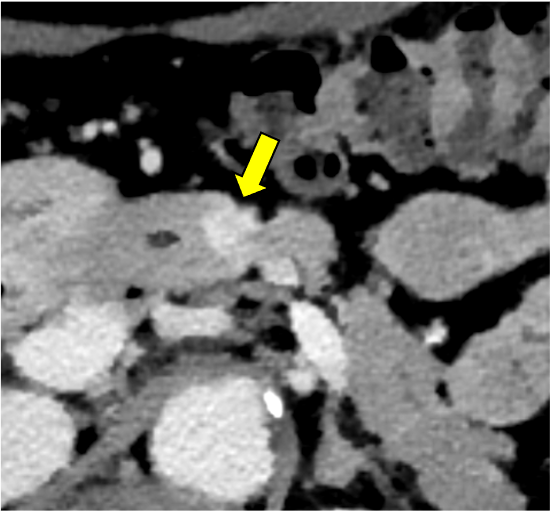

膵ダイナミックCTの膵実質相120kVp画像(図1)で膵体部に限局性萎縮(赤矢印)を認めるが、膵癌を疑わせるような低吸収域は同定できない。遅延相120kVp画像(図2)では萎縮部近傍にごく淡い高吸収域(黄矢印)を認め、線維性間質に富む膵癌の可能性が示唆される。Dual-energy CTの仮想単色低エネルギー画像(図3)およびヨード密度画像(図4)では遅延濃染域が明瞭化しており、膵癌の診断確信度が向上する。膵体尾部切除術が施行され、高分化型浸潤性膵管癌(腫瘍径6mm、pT1a)と最終診断された。術後、補助化学療法が行われ、現在まで無再発で経過している。

膵癌は最も予後不良な悪性腫瘍のひとつであり、早期診断が極めて重要である。CTは膵癌診断の主軸を担う画像診断モダリティで、病変の検出や病期診断などに必要不可欠な役割を果たしている。膵癌は線維性間質に富む腫瘍であり、造影CTで早期相から遅延相にかけて漸増性に増強される。これに対して正常膵は膵実質相で造影効果が最大化し、その後漸減する。このため、典型的な膵癌は膵実質相において低吸収を示し、このタイミングで最も明瞭に描出される。しかし、サイズの小さな早期膵癌は線維性間質や壊死が少なく、膵実質相で等吸収を示す傾向がある。その場合、限局性の膵萎縮や淡い遅延性増強効果が病変検出の鍵となるが、これらの変化はわずかなことが多く、従来のsingle-energy CTでは、早期膵癌を高い確信度で診断するのが困難である。

CT技術や撮像プロトコル設定について